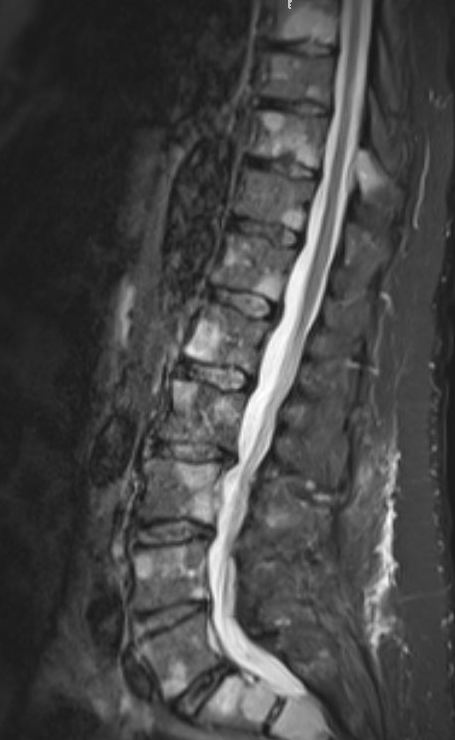

Whole body MRI

- usually long bone or vertebrae

- in spine commonly present with rapidly progressive paraplegia

- this is more common in plasmacytoma then multiple myeloma

- stabilization of spinal lesions